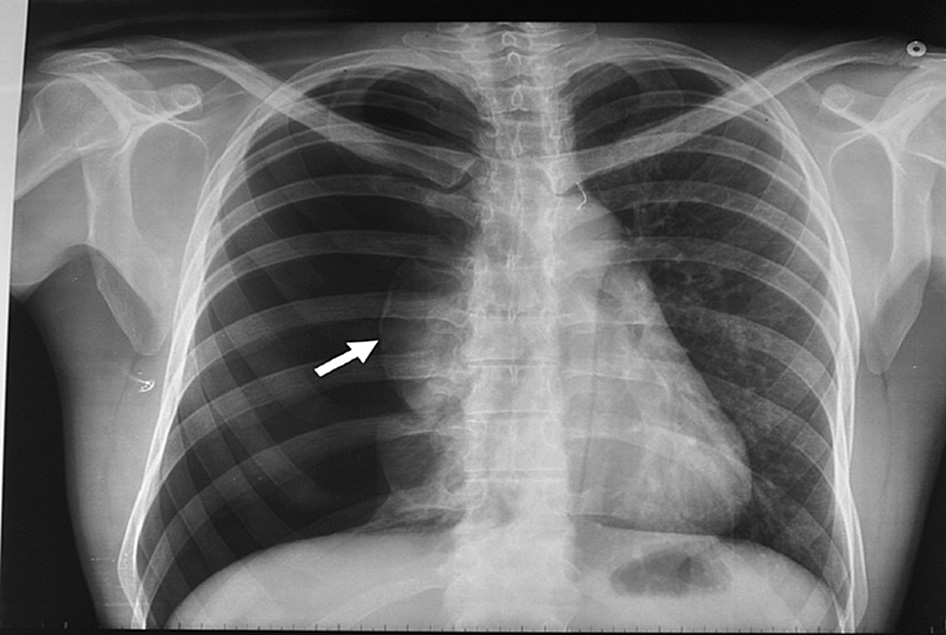

Neumotórax espontáneo: aspiración con aguja vs drenaje con tubo

El tratamiento inicial de aspiración con aguja obtiene mejore resultados inmediatos y acorta los tiempos de internación. European Respiratory Journal, abril de 2017